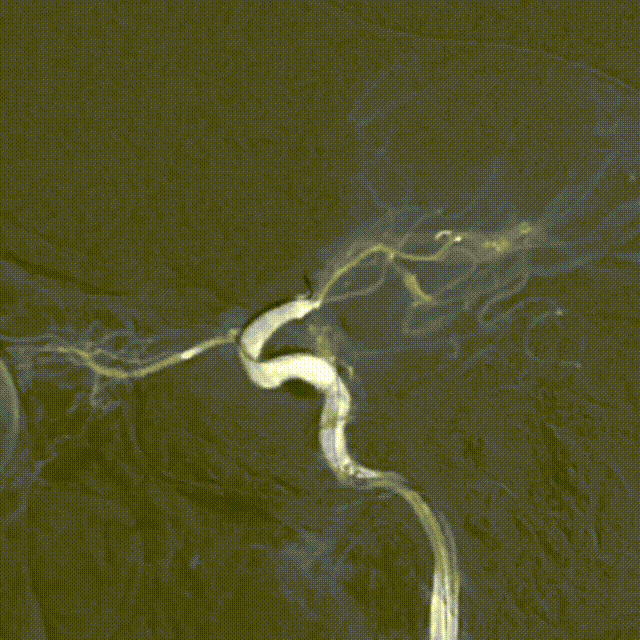

SacSpeed®球囊扩张导管 2.0*9mm球囊到位过程。

SacSpeed®球囊扩张导管 2.0*9mm球囊到位造影:血管再闭塞。

SacSpeed®球囊扩张导管缓慢扩张过程中见明显腰线。

球扩后造影:狭窄明显改善,前向血流明显好转,未见血栓征象,球囊部分回收支架,撤出。